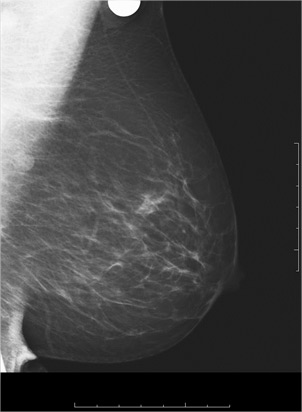

1/ La mammographie : elle reste l’examen de référence.

La mammographie par tomo-synthèse prend les images de la glande mammaire sous différents angles. Il s’agit d’un progrès technique considérable, permettant une meilleur visualisation et appréciation des images par rapport à la mammographie numérique « classique » en deux dimensions.

Le radiologue fera une lecture comparative des clichés des seins droit et gauche et recherchera :

une image stellaire évocatrice de lésion cancéreuse,

une opacité irrégulière,

des micro-calcifications qui peuvent être, dans une majorité, d’origine bénigne, mais dont le regroupement, la forme ou l’évolution en comparaison d’un examen précédent, peuvent faire suspecter une lésion débutante,

- les images régulières dans leur forme ont une traduction échographique très spécifique et évocatrice de kystes liquidiens ou d’adénofibromes bénins.

Un cancer visible en mammographie sous forme d’une masse opaque (blanche).

Un cancer visible en mammographie sous forme d’une masse opaque (blanche)